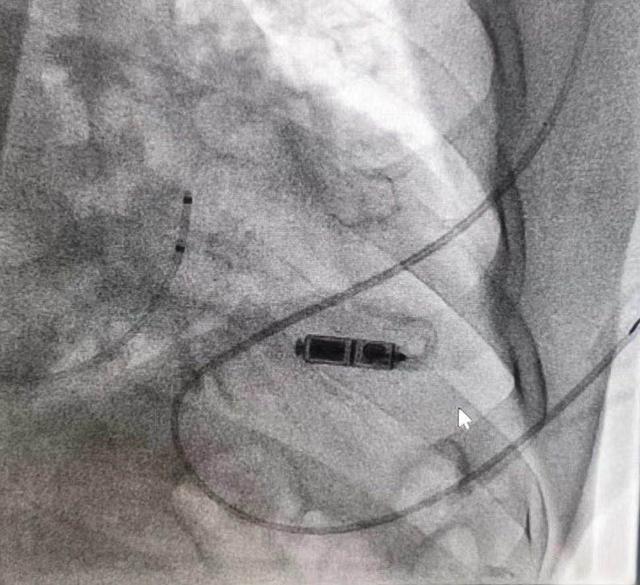

常州二院心内科一周内连创佳绩。继日前完成常州首例 Micra 无导线起搏器植入后,21 日又成功为 99 岁老人植入这款全球最小无导线起搏器,刷新了全国同类手术最高年龄纪录。

左边为 Micra 无导线起搏器

8 月 21 日中午,心内科主任纪元带领的由李海燕、王芳芳等专家组成的团队为老先生实施了手术。他们通过股静脉穿刺,将起搏器通过导管送入到心室腔,最后借助 X 光透视画面确认调整,抵达右心室最佳位置,成功植入起搏器。全程仅用了 60 分钟。目前,刘老先生自我感觉良好,已能正常活动。